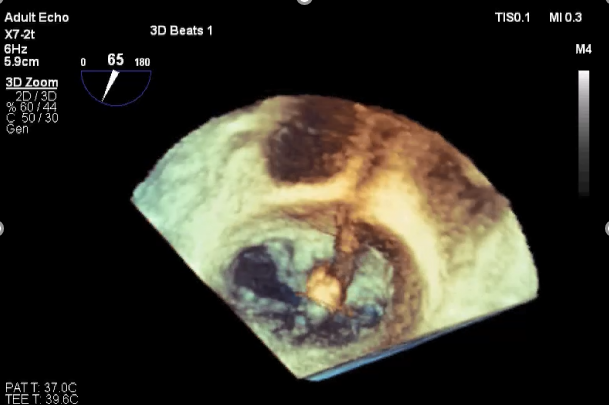

三维超声心动图显示第一枚XTR夹子释放,残余返流主要位于外侧

三维超声心动图显示第二枚XTR夹子释放